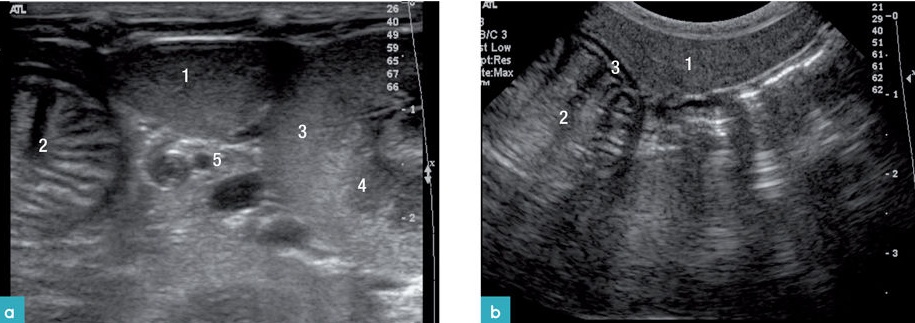

고양이의 비장은 좌측 복벽에서 위의 분문과 가까이 위 아랫부분에 그리고 좌측 신장의 앞쪽 부분에 위치합니다(그림 1).

비장을 스캔하기 위해, 환자의 위치를 우측 외측상 혹은 등쪽을 눕힌 자세(dorsal recumbency)로 위치시킵니다. 비장이 비교적 얕은 부위에 존재하므로 고주파 프로브를 사용하는 것이 좋습니다. 비장은 머리부터 꼬리까지 철저히 횡단면, 종단면으로 스캔합니다.

b) convex transducer로 스캔한 비장. 1. 비장, 2. 위의 내강, 3. 위의 추벽

스캔 시 비장의 모양은 혀(tongue) 모양을 가지며, 꼬리부분이 머리 부분과 몸통보다 넓습니다. 횡단면은 삼각형 모양으로 개의 비장보다 작으며, 위치가 일정합니다. 비장의 머리 부분은 위비장 인대에 의해서 위에 고정되어 있으며, 몸통과 꼬리는 많은 유동성이 있으나, 그 유동성의 정도는 개보다 적습니다. 건강한 고양이에서 비장은 얇고, 고에코성의 캡슐표면으로 부드러운 모양으로 잘 확인이 되며, 깨끗한 경계 부위를 가집니다. 비장의 실질은 치밀하고 동질성의 미세한 과립성의 echotexture를 가집니다(그림 2).